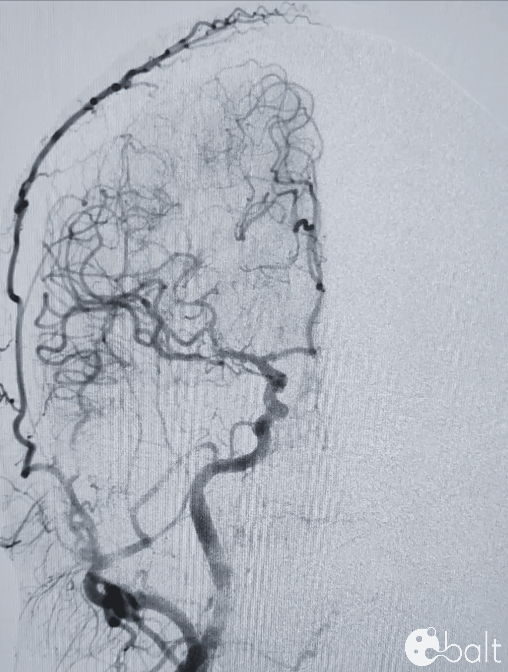

术前影像

颅脑DSA

临床诊断:右侧大脑中动脉M1分叉部宽颈动脉瘤

瘤体大小:5.04*4.56mm。